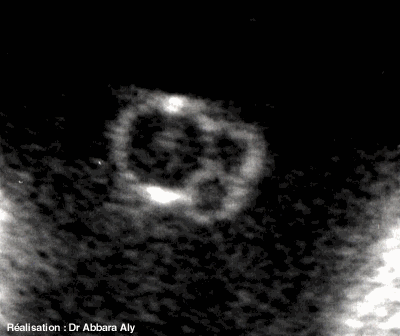

Coupe simple du cordon ombilical fœtal